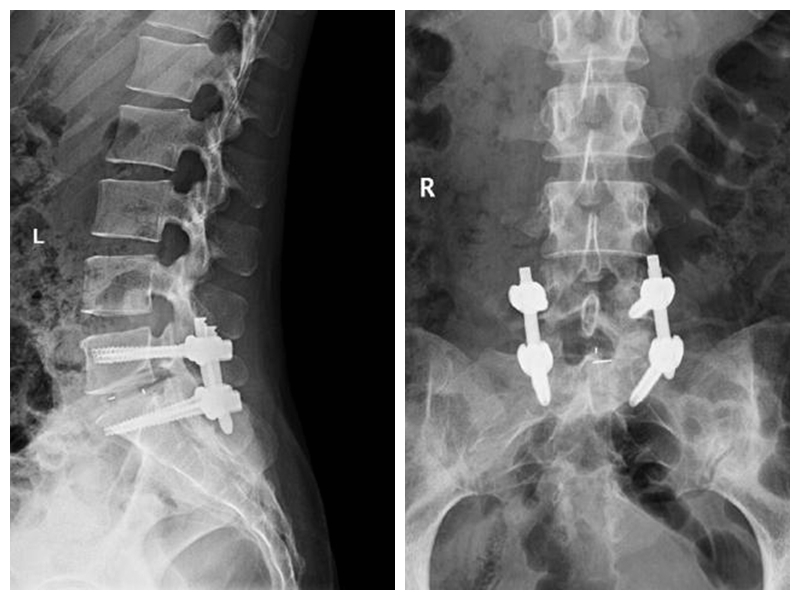

經(jīng)皮椎體成形術(shù)及球囊復(fù)位、椎體后凸成形術(shù)

經(jīng)皮椎體成形術(shù)及球囊復(fù)位、椎體后凸成形術(shù)適用于老年性骨質(zhì)疏松性椎體壓縮骨折及腫瘤性病理性壓縮骨折。手術(shù)創(chuàng)傷小,術(shù)后疼痛緩解迅速、恢復(fù)時(shí)間短,療效可靠。使患者及早下床活動(dòng),改善患者的生活質(zhì)量,減輕患者家庭及社會(huì)的負(fù)擔(dān)。

典型病例:患者劉**,女,70歲,因“在家滑倒摔傷腰背部疼痛活動(dòng)受限2天”步行入院。查體:腰3、4棘突壓痛,椎體及椎旁壓痛明顯,雙下肢肌力、感覺正常。

術(shù)后第1天患者下地行走,腰痛明顯緩解。(骨科二區(qū) 孫進(jìn))